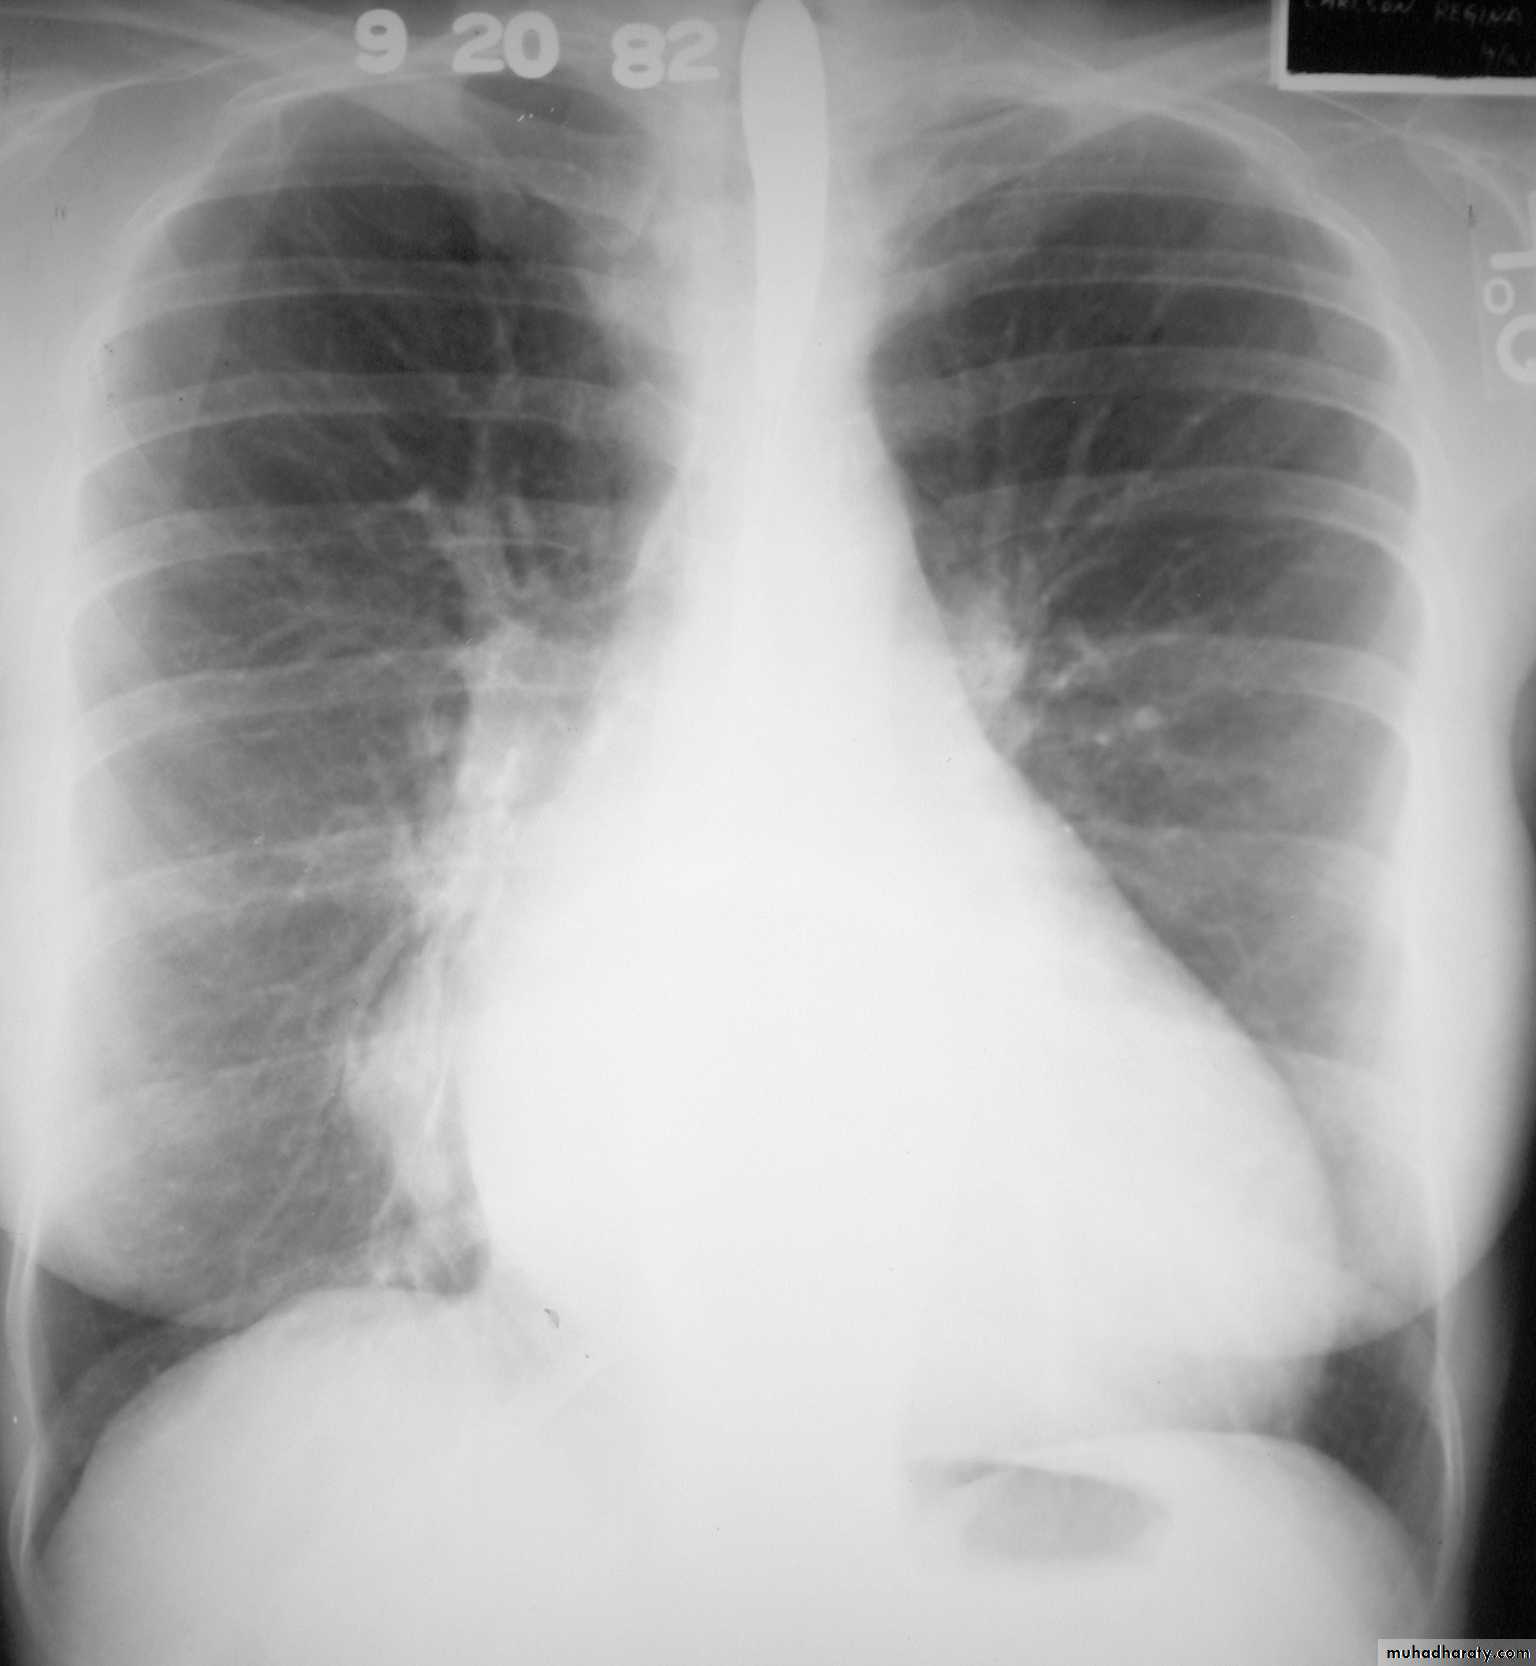

Normal thymus gland ( sail shape sign )

Heart Assessment & measurement

The heart has a somewhat conical form and is enclosed by pericardium. It is positioned posteriorly to the body of the sternum with one-third of it is situated on the right and two-thirds on the left of the midline .

Cardiothoracic ratio (CTR) = Cardiac Width : Thoracic Width

A CTR of greater than 1:2 (50%) is considered abnormal. This however, assumes the projection is Posterior-Anterior (PA), and that cardiac size is not exaggerated by factors such as patient rotation or an incomplete breath in .

The cardiothoracic ratio aids in the detection of cardiomegaly, or more broadly,enlargement of the cardiac silhouette. .

Enlargement of the cardiac silhouette on chest x-ray can be due to a number of causes :

cardiomegaly (most common cause by far)pericardial effusion